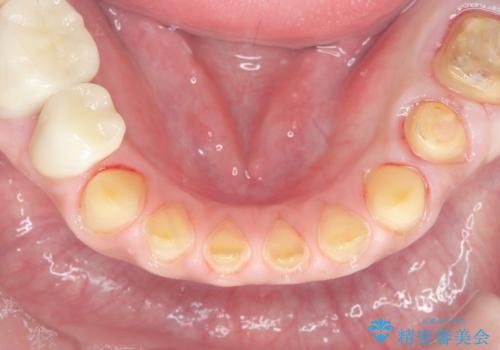

歯ぎしりですり減った 前歯の見た目を回復したい

- 歯ぎしり・嘔吐症により歯がすり減ってしまい、色調・見た目を改善したいと来院されました。

神経を温存したまま仮歯に置き換え、噛み合わせの安定を確認したのちに すり減りに強いジルコニアクラウンで最終的な仕上げを行います。